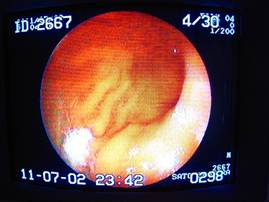

胃の中に入ったところ。

(大彎部~幽門に向けて)